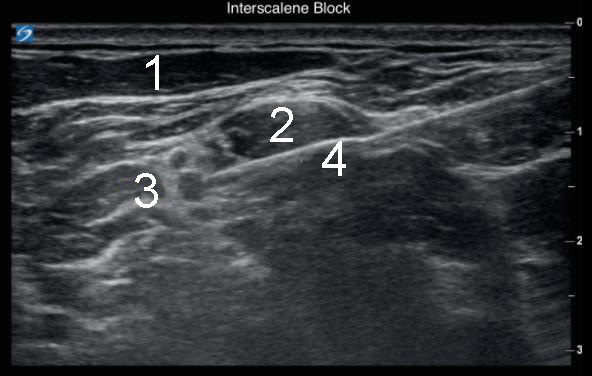

Left Interscalene Block with Needle 2 Image

1. Sternocleidomastoid Muscle (SCM)

2. Middle Scalene

3. Brachial Plexus

4. Needle